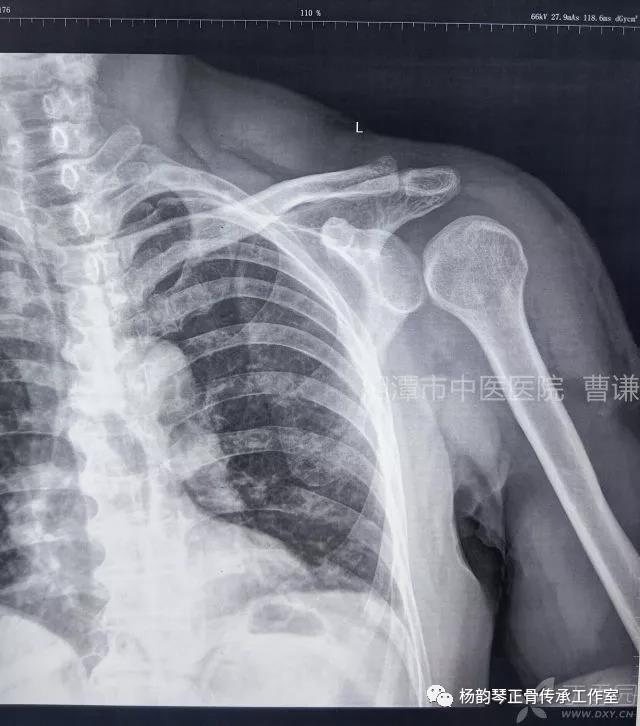

简要病史:骑摩托车跌倒致左肩部肿痛,活动受限,就诊于当地医院,拍片及磁共振检查后诊断为肩袖损伤及肩关节半脱位,予以悬吊固定,因症状缓解不明显就诊于我院。外院拍片情况如下:

应该说是一个典型的“灯泡征”影像,但是并未引起注意。